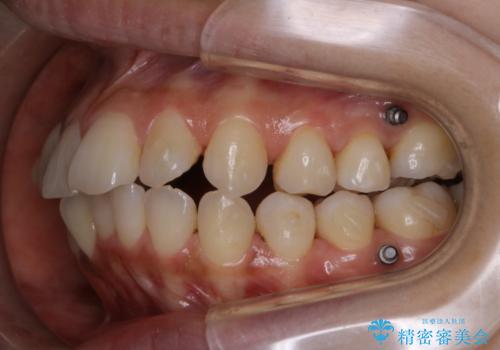

- インビザラインでのマウスピース矯正中の方です。歯についてしまったステインが気になり綺麗にしたいとのことでした。PMTC60分コースを行いました。

PMTC(保険外治療)は、毎日の歯磨きで落としきれない汚れや、コーヒ、紅茶・タバコのヤニなどの着色も除去します。目には見えない歯と歯の間・歯肉の境目・インビザライン中はアタッチメント周囲などに残っているプラーク(歯垢)もしっかり取り除きます。PMTCでは専門的な機械や材料を使用して、徹底的に汚れを除去するため、虫歯・歯周病・口臭予防などにつながります。